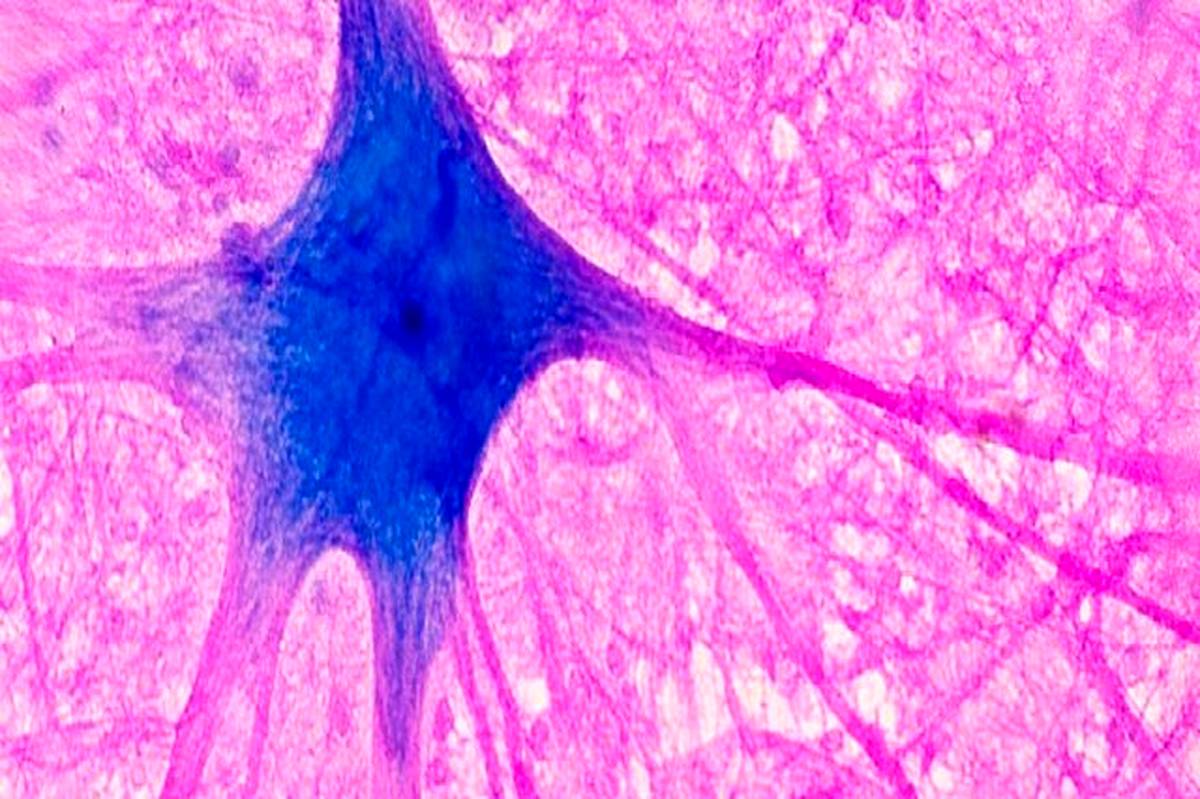

«متیلن بلو» میتواند از مانع حفاظتی اطراف مغز(سد خونی مغز) عبور کند و وارد آن شود. دانشمندان همچنین دریافتهاند که این ماده میتواند از «میتوکندریها»(mitochondria) که بهعنوان موتورهای سلولی توصیف میشوند، محافظت و پشتیبانی کند. این ماده ممکن است به «میتوکندریها» کمک کند تا انرژی را برای استفاده سلولها تولید کنند. به همین دلایل، دانشمندان در حال مطالعه تأثیر «متیلن بلو» بر مغز هستند.

بیشتر آنچه درباره تأثیرات این ماده بر مغز تاکنون شناخته شده است، از مطالعات بر روی موشها و سلولهای رشد یافته در ظروف آزمایشگاهی ناشی میشود. مطالعات بر روی جوندگان همچنین نشان داده است که این ماده میتواند از مغز در برابر آسیب ناشی از ضربه مغزی محافظت کند. با این حال، هیچ مطالعهای تاکنون بررسی نکرده است که آیا این ماده میتواند مغز انسانها را از آسیب مغزی یا سکته مغزی محافظت کند یا خیر.